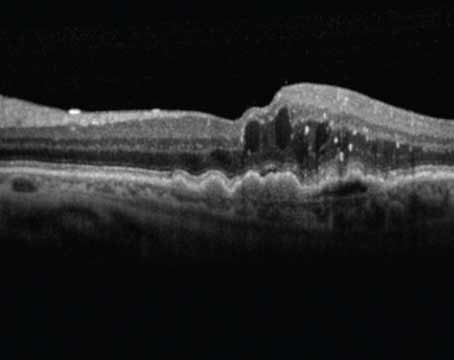

How OCT is improving early characterization of GA lesions